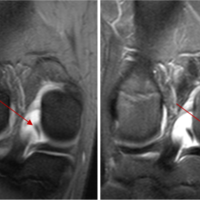

Surgical procedures were performed under general anesthesia. In the arthroscopic group, anterolateral and anteromedial portal were created. In the open surgery group, either an anteromedial or anterolateral approach was used. Both groups underwent joint irrigation with saline, and infected tissue was debrided as necessary. In the open surgery group, arthrotomy was followed by wound closure with a drain.